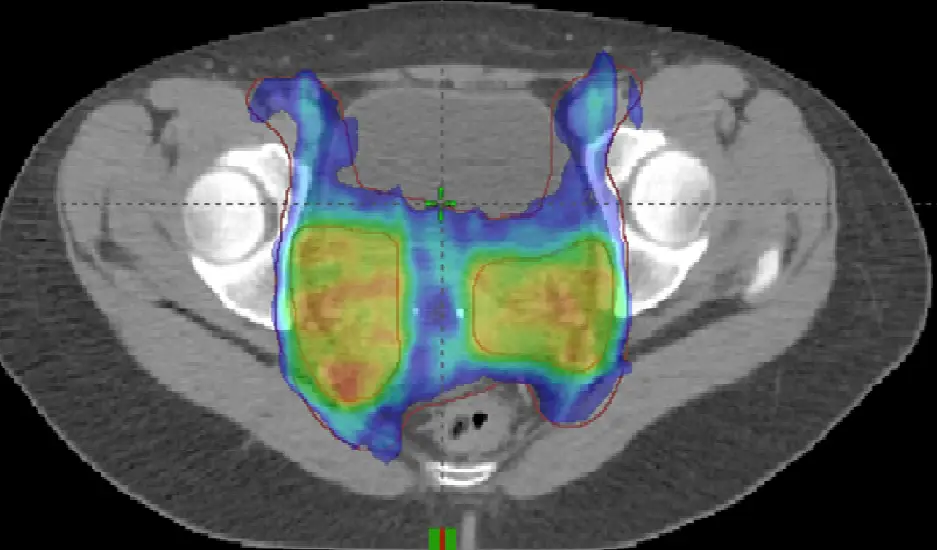

本題提供一張骨盆腔的軸狀電腦斷層(Axial CT)影像,並疊加了放射治療的劑量分佈圖(Color wash)。

- 劑量順形度:劑量分佈呈現高度順形(Conformal),並且在前方與後方產生了明顯的凹陷,將高劑量區緊密包覆在兩側骨盆腔淋巴結與中央的子宮旁組織周圍。這明顯是強度調控放射治療(IMRT)或體積調控弧形放射治療(VMAT)的特徵。

- 整合加強治療技術(SIB):從色彩分佈可以觀察到兩種明顯的劑量階層:外圍的藍色區域為基礎處方劑量(通常用於預防性骨盆腔淋巴結照射),而兩側深黃色/橘紅色的區塊則是針對局部區域(如已轉移的淋巴結或高風險區)給予更高的劑量。在同一個治療計畫、同一次給予不同的標靶不同劑量,即為 SIB 技術。

- 脹膀胱(Full Bladder):在標靶區域的正前方(影像上方),可見一個體積巨大、呈現均勻水液密度的深灰色構造,這是脹滿的膀胱。骨盆腔放射治療標準流程通常會要求病患「脹膀胱」,目的是將小腸往上及往前推擠,使其離開輻射高劑量區,藉此減少腸胃道副